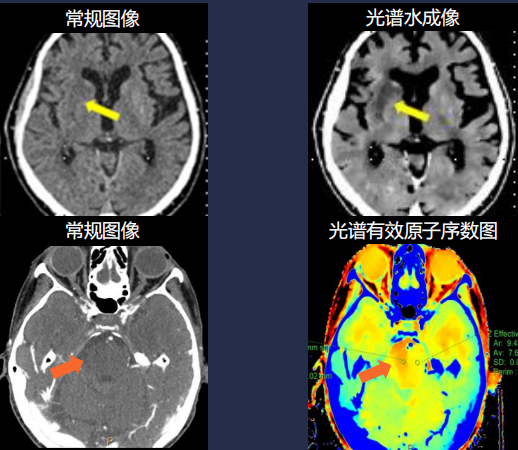

突破单参数常规CT极限 多参数全流程卒中关护

皓克CT平扫检出超急性期缺血性卒中及出血性卒中,CTA扫描可以同时得 到脑血管、脑灌注、活动性出现鉴别等多重信息,避免重复检查,帮助病 患的争取宝贵时间,及时得到救治,挽救患者生命。神经诊断临床效能媲美MR(平扫检出超急性期缺血性卒中,CTA评价脑灌注,预后高密度鉴别,全程关护)